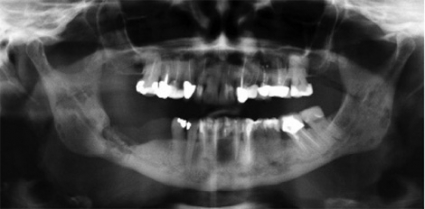

Extraktionsalveol som inte läkt ut

I ca 90 procent av fallen lokaliserades käkbensnekrosen till mandibeln. Den typiska kliniska bilden har varit en extraktionsalveol, som efter tandextraktion inte läkt ut. Med tiden (veckor till månader) exponeras allt mer käkben i anslutning till alveolen. Detta sker ibland symtomfritt, men ofta med smärta och lokal svullnad och ibland pus. Preliminär diagnos har ofta varit en osteomyelit med sekvestrering, som dock inte svarat på antibiotikabehandling. Kliniken liknar i flera avseenden även den man ser vid osteoradionekros (Figur 1 och 2).